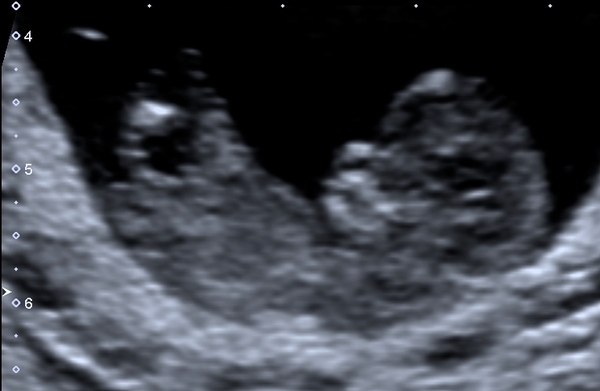

I'm just growing a tinker!!! All snug in there, bouncing around, and even gave us a wave, and can't find any reason for the bleeding.

After being paranoid as symptoms disappeared this week we booked a second early scan. Paranoid mumma!!

So we're now 9+3 instead of 8+6.

String little heart beat and baby looked like it was dancing away!